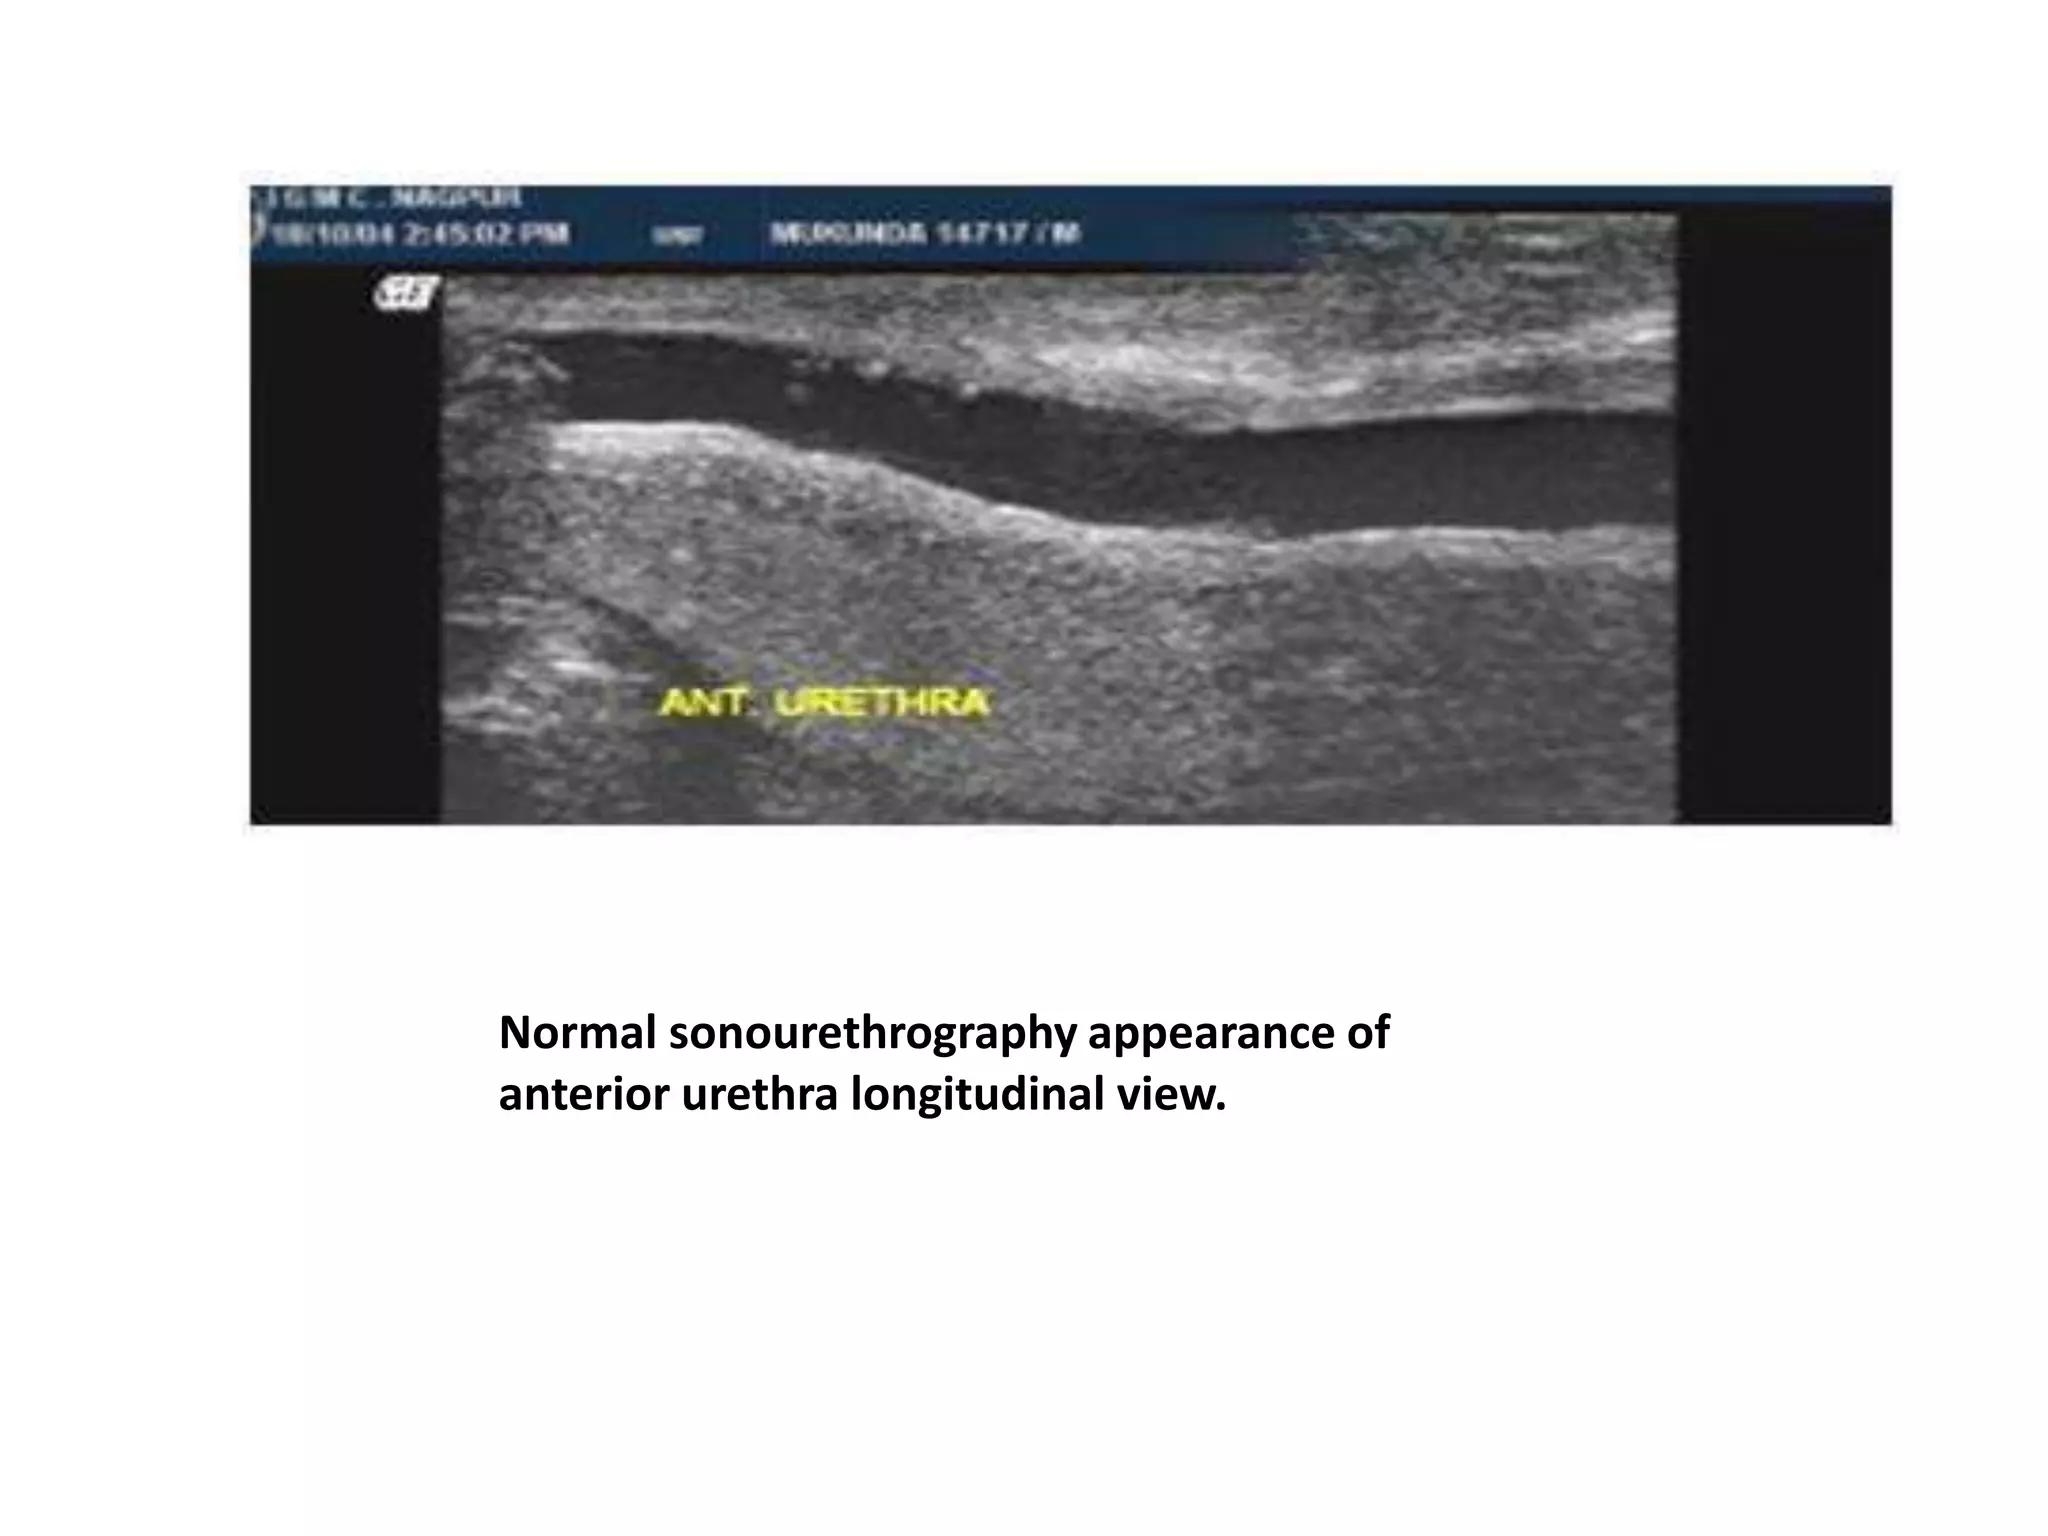

Sonourethrography in Evaluation of

Abnormalities of Anterior Male

Urethra.

• The technique involved is the use of a 5 MHz linear

array transducer applied to the dorsal surface of the

penis.

• Images are obtained during retrograde instillation of

normal saline.

• As a dynamic, three-dimensional study, which can be

repeated without radiation exposure,

sonourethrography offers important advantages over

conventional techniques.

• Panoramic reconstruction of the sonographic images is

done for better understanding of urethral pathologies.

Normal sonourethrography appearance of

anterior urethra longitudinal view.